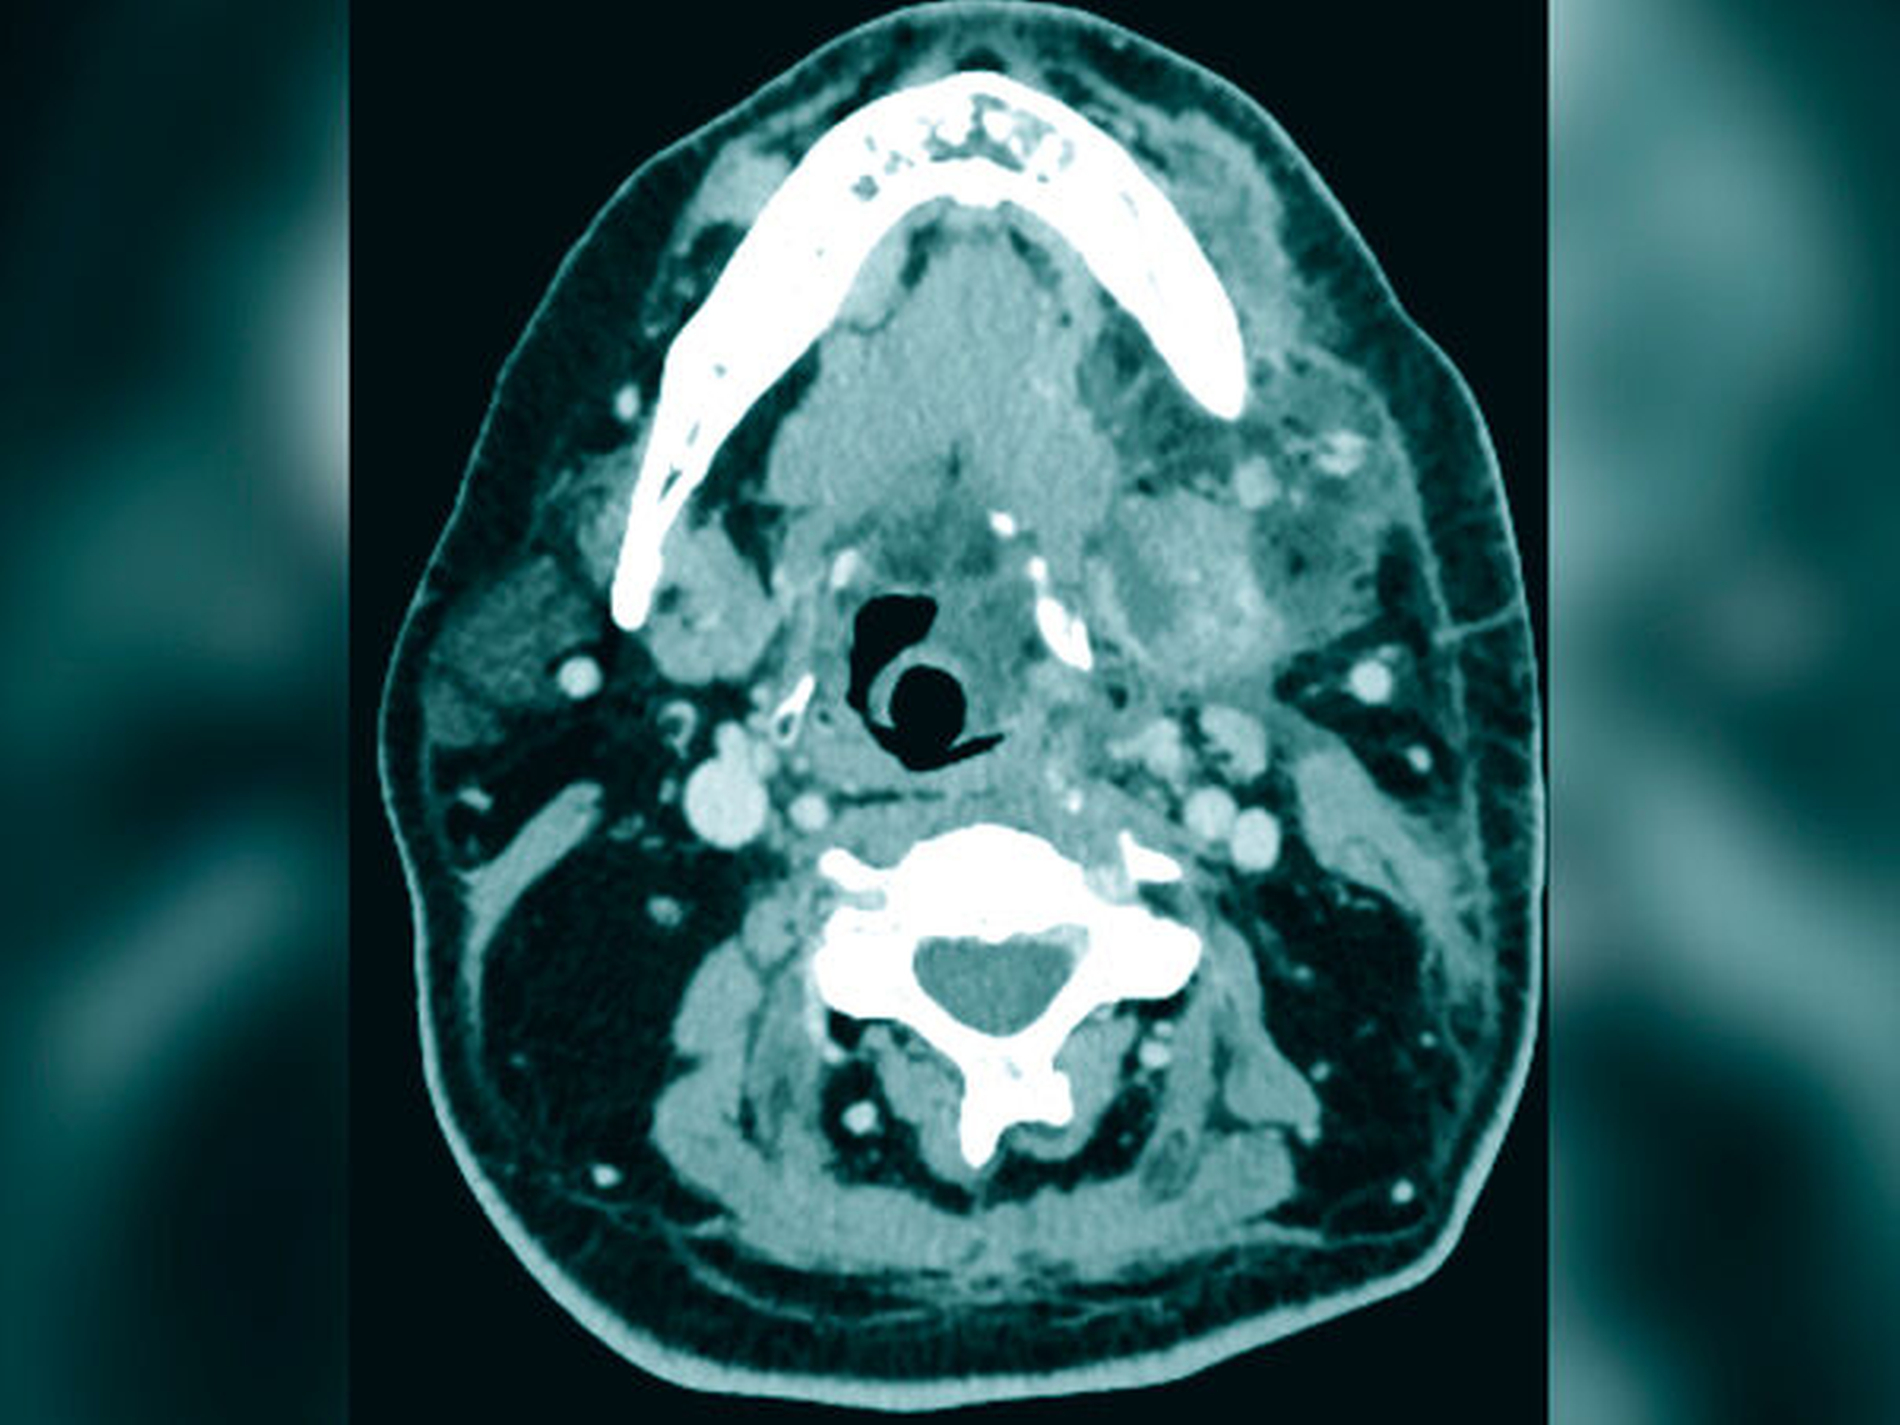

Eine angefertigte Panoramaschichtaufnahme zeigte ein konservierend und prothetisch unvollständig versorgtes Gebiss mit einem wurzelkanalbehandelten Zahn 36 und einer apikalen Osteolyse (Abbildung 1). Angesichts des ausgedehnten Abszessgeschehens wurde eine notfallmäßige Computertomografie zur erweiterten Diagnostik durchgeführt. Hier zeigte sich ein großflächiger Abszess des linken Unterkiefers mit einer Ausbreitung in die Tonsillenregion sowie in die Halslogen mit begleitenden einschmelzenden Prozessen (Abbildung 2). Zusätzlich zeigten sich im initial angefertigten Blutbild des Patienten ein Procalcitonin von 10 ng/ml, eine Blutglukose von 1.034 mg/dl sowie ein HBA1c-Wert von 13 Prozent. In der Zusammenschau der Befunde konnte somit von einem beginnenden septischen Krankheitsbild ausgegangen werden.

Im initialen Stadium ist eine rasche Diagnosefindung entscheidend für die Prognose der Patienten. Eine erweiterte Diagnostik mittels Computertomografie ist schnellstmöglich anzustreben. Die radiologische Symptomatik zeigt neben Abszessformationen – wie im vorgestellten Fall – vor allem Lufteinschlüsse und Einschmelzungen mit Flüssigkeitsansammlungen in den tieferen Faszienanteilen. Das umgebende Fettgewebe und die umgebende Muskulatur stellen sich oftmals verdickt dar [Fais et al., 2018]. Obgleich diese radiologischen Phänomene pathognomonisch für die Erkrankung sind, finden sie sich nicht in allen Patienten. Eine chirurgische Exploration führt in der Regel zur Diagnose. Bei Eröffnung der Kompartimente lassen sich neben Pus und Blut auch nekrotische Muskulatur und subkutanes Gewebe darstellen.